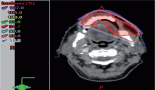

We report a case of pyrexia of unknown origin presenting with lactic acidosis and hypoglycaemia. He further developed Guillain–Barre syndrome (GBS) and Hemophagocytic lymphohistiocytosis (HLH). The bone marrow biopsy ultimately reported Diffuse large B cell lymphoma (DLBCL). A 74-year-old gentleman visited the hospital in January 2024 with a fever since 2 weeks. He further developed hypoglycemic episodes and lower limb followed by upper limb weakness. On physical examination, he was febrile, tachypnoec with hepatomegaly and bilateral lower limb weakness with grade 3 power proximally and extensor plantar reflexes. Peripheral smear showed a leucoerythroblastic picture and 3% atypical lymphoid cells. Procalcitonin, lactate dehydrogenase and Ferritin were markedly elevated, suggestive of HLH. The bone marrow biopsy ultimately revealed DLBCL. He was diagnosed with GBS, Warburg phenomenon and HLH secondary to DLBCL. Intravenous steroids were started for secondary HLH and after he became hemodynamically stable was initiated on chemotherapy with Rituximab, Cyclophosphamide, Doxorubicin, Vincristine, Prednisolone (R-CHOP) regimen. After four cycles of R mini-CHOP, positron emission tomography–computed tomography showed a good response. Further two cycles of R mini-CHOP was given with methotrexate for central nervous system prophylaxis. This case portrays an atypical presentation of DLBCL with Warburg syndrome, GBS and HLH. Despite the adverse clinical course, the patient responded favourably to chemotherapy.